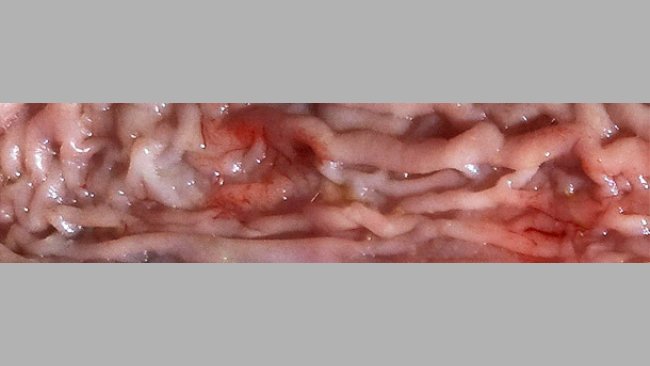

Klinischer Fall: Auswirkung klinischer und subklinischer Ileitis auf demselben Betrieb

Ileitis tritt in verschiedenen Formen auf, häufig kommen eine subklinische und eine klinische Form gleichzeitig vor.